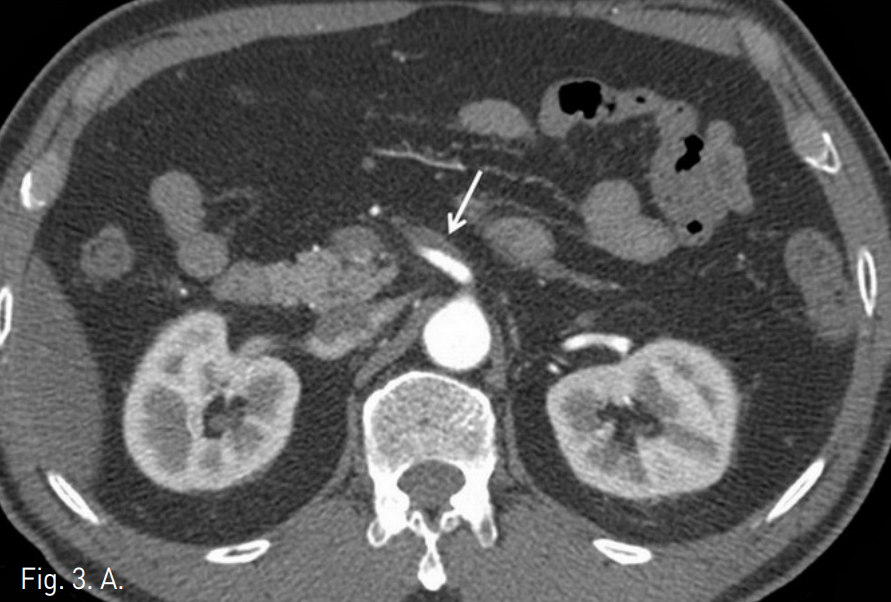

복부 CT에서 상장간막동맥(superior mesenteric artery, SMA)의 박리가 있었으며 중간결장동맥(middle colic artery)의 기시부가 경도로 좁아져 있고 가성 내강과 진성 내강의 혈류가 관찰되었다(Fig. 1). 같은 날 시행한 혈관조영술에서 상장간막동맥 기시부부터 회결장동맥(ileocolic artery) 분지부까지 침범한 동맥박리를 확인 하였다(Fig 2). 이 밖에 복강동맥과 하장간막동맥에는 특이 소견은 발견 되지 않았으나 변연 동맥 여러 곳이 동맥경화에 의한 좁아져 있었다. 소장과 대장의 동맥혈류가 유지되고 있어 스텐트삽입술은 시행하지 않았으며, 수축기 혈압 110mmHg, 심장박동 수 50~60회로 유지하며 보존적 약물치료를 하였다. 환자의 복통은 진정되었으며 7일 후 퇴원하였다. 5개월 후 추적검사로 시행한 복부 CT에서 상장간막동맥의 박리피판이 여전히 관찰되며 진성 내강과 가성 내강의 개통성을 확인할 수 있었고 기타 변연 동맥의 폐색은 없는 것이 확인되었다. 하지만 1년 추적 복부 CT에서는 가성 내강을 따라 혈전이 형성되었고(Fig. 3) 원위부로 혈관 폐색의 소견은 보이지 않았으며 장관의 허혈이나 경색 소견 또한 관찰되지 않았다. 2년 추적 CT에서 상장간막동맥은 정상화되었으며 박리나 동맥류 소견은 관찰되지 않았다.

Fig. 3

A, B. (A) The axial image of the one-year follow-up abdominal CT shows thrombosis of the entire false lumen of SMA (arrow). (B) The two-yer follow-up CT shows normal SMA without dissection or aneurysm (arrow head).